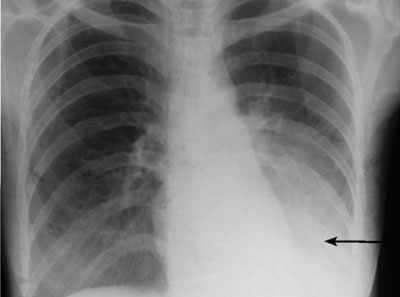

Опасным заболеванием, которое способно лишить человека жизни, является пневмония, затемнение легкого, проявляющееся на рентгеновском снимке, может быть признаком не только воспалительного процесса, но и других более серьезных патологических изменений. Чтобы вовремя выявить болезнь, необходимо регулярно проходить профилактическое медицинское обследование. Флюорография или рентген покажут изменения, если они есть. Одного снимка, как правило, недостаточно для установления точного диагноза. Врач назначает дополнительные процедуры, которые помогают выяснить причину затемнения в легких. Только после проведения полного комплекса диагностики доктор назначает курс терапии.

В норме кислород полностью заполняет полость легкого. При поражении тканей воздух не может попасть в определенную часть органа. Образовывается уплотнение, которое может иметь разную форму и размер. Это уплотнение и является затемнением на снимке. Его природа может быть самой разной. Наиболее часто этот показатель свидетельствует о развитии пневмонии. Хороший специалист без труда поймет это.

Врач делает выводы на основании тщательного осмотра рентгеновского снимка или результатов флюорографического исследования. Соотнеся вид затемнений и жалобы пациента, доктор выбирает тактику дальнейшего обследования и лечения.

Затемнение легкого на рентгене или флюорографии представляет собой изменение плотности легочной ткани, которое может указывать на наличие патологических процессов в легких, включая пневмонию.